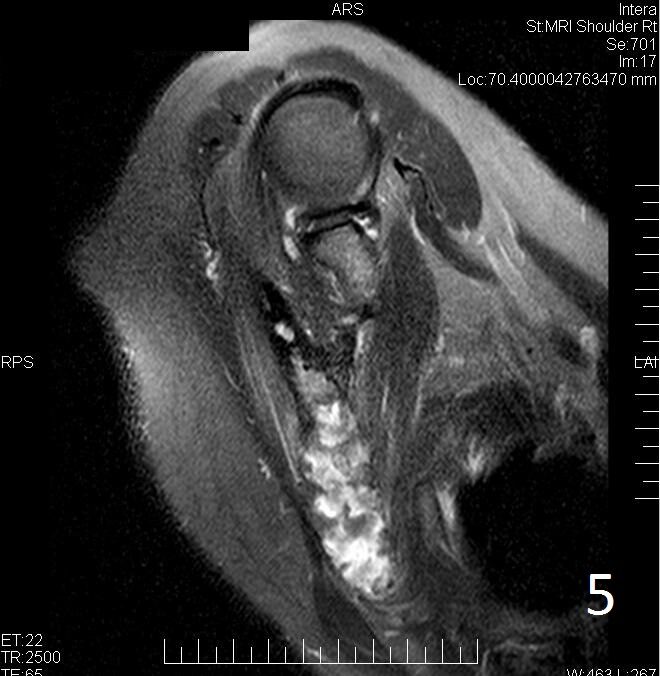

MRI

• Variable heterogeneous signal on T2 (Fig. 5)

Fig. 5. Same lesion on Axial T2W FS shows heterogenous signal.